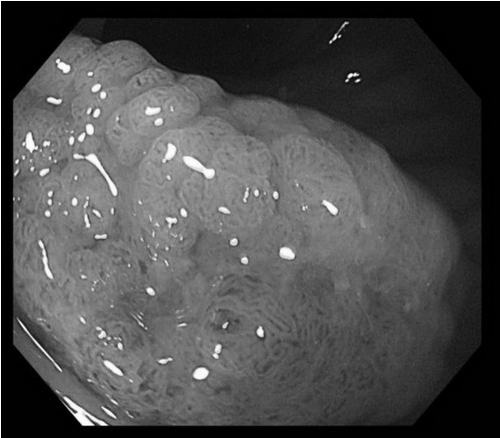

67歲因咳嗽在花蓮慈院就診病人,經大廳熱心癌症快速篩檢服務人員詢問後同意接受免費糞便潛血篩檢,因潛血陽性進一步大腸鏡檢查,最後洪勝睿醫師發現3公分扁平結腸腫瘤。(洪睿勝醫師提供)